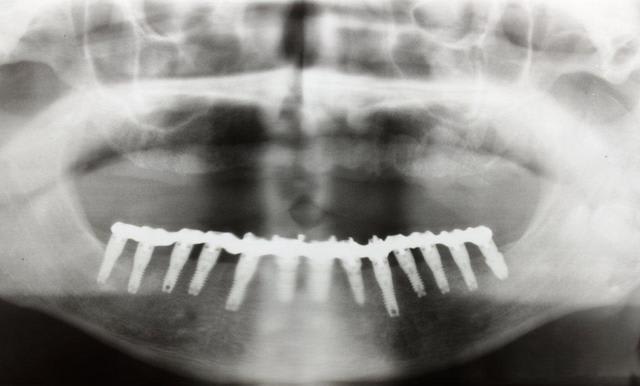

Juste pour vous dire à tous que je vis toujours

Un gros rail d os et tout posé à main levée

Img 1414 vvi8f3 - Eugenol

Img 1428 aah6ry - Eugenol

Img 1433 wp5tki - Eugenol

Img 1435 kjo20z - Eugenol

Img 1436 wdm8bi - Eugenol

Ton patient va mourir d'une overdose de titane ;-)

Sérieusement, je m’interroge sur la validité bio-mécanique de placer 13 implants à la mandibule, et de tout relier cela d'un bloc.

Je crois que 8 implants soient amplement suffisants : meilleur espacement entre les implants pour l'entretient et la maintenance paro